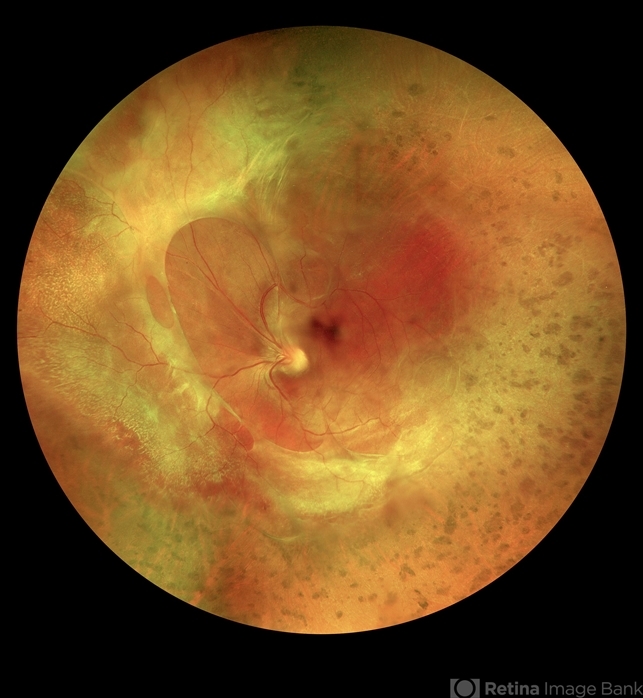

- familial exudative vitreoretinopathy (FEVR)

- Carmelina Timboli, Vitreous Retina Macula Specialists of Toronto

- Optos California (Optos PLC, Edinburgh, UK)

- Widefield montage pseudocolor image of a 35-year-old woman with prior history of FEVR.